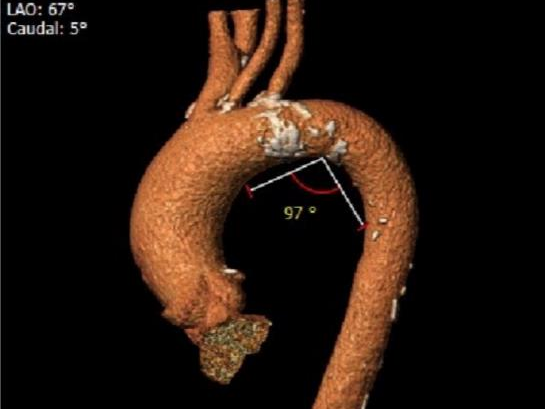

外周血管及主动脉弓解剖: